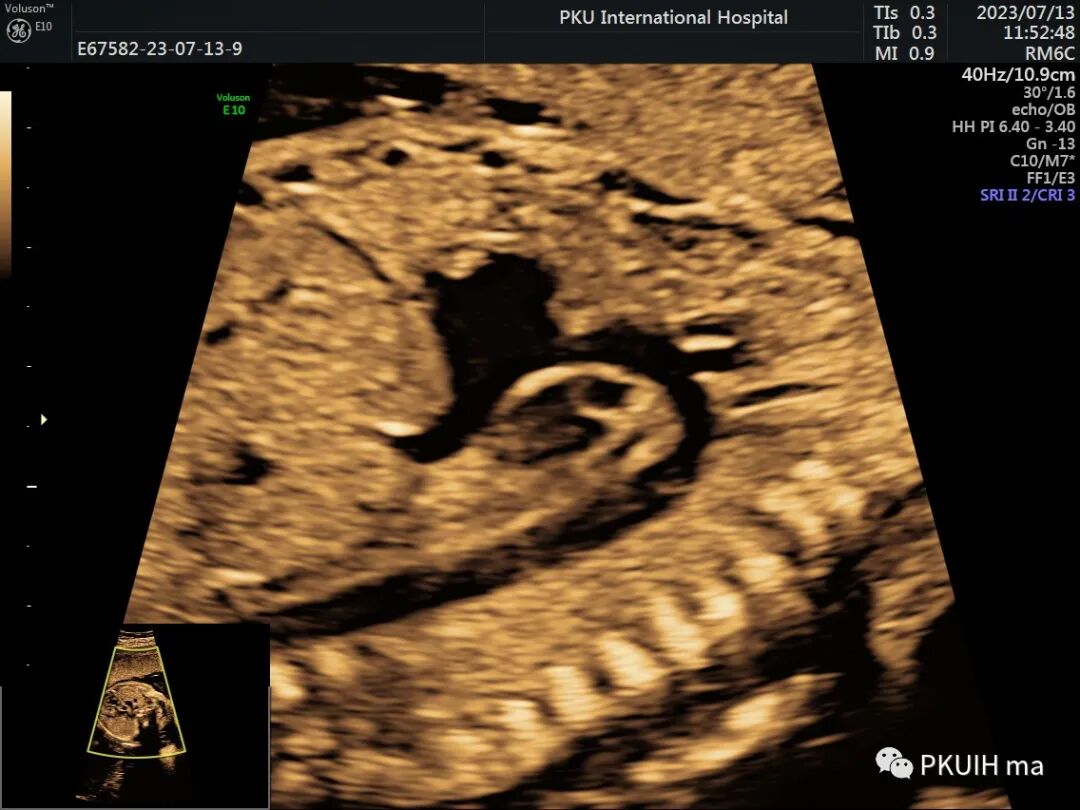

另外,主动脉弓长轴切面显示峡部与降主动脉连接处形态异常,主动脉弓缩窄处与粗大的降主动脉相连,局部形成环形缩窄或后壁向管腔内形成“嵴”样隆起,故称之为“缩窄环”,又称 “支架征” 。如下图